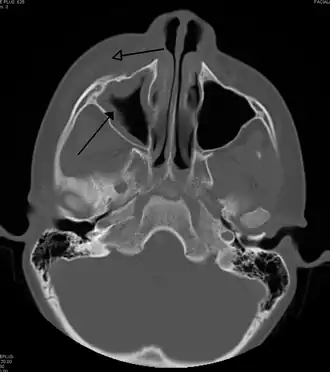

| Periorbital cellulitis caused by a dental infection (also causing maxillary sinusitis) | |

Periorbital cellulitis, or preseptal cellulitis, is an inflammation and infection of the eyelid and portions of skin around the eye anterior to the orbital septum.[1] It may be caused by breaks in the skin around the eye, and subsequent spread to the eyelid; infection of the sinuses around the nose (sinusitis); or from spread of an infection elsewhere through the blood.

Periorbital cellulitis must be differentiated from orbital cellulitis, which is an emergency and requires intravenous (IV) antibiotics. In contrast to orbital cellulitis, patients with periorbital cellulitis do not have bulging of the eye (proptosis), limited eye movement (ophthalmoplegia), pain on eye movement, or loss of vision. If any of these features is present, one must assume that the patient has orbital cellulitis and begin treatment with IV antibiotics. CT scan may be done to delineate the extension of the infection.